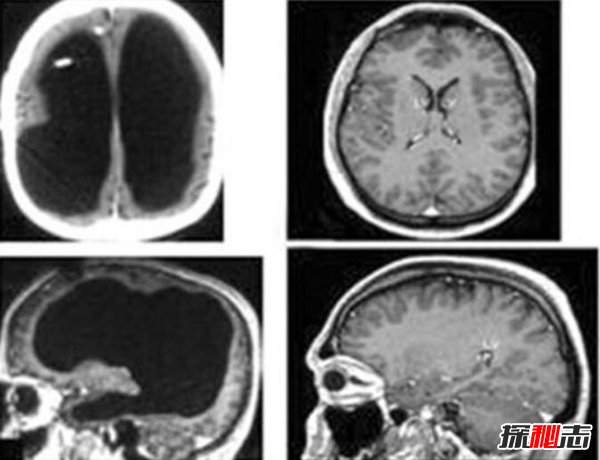

这下子抓捕叶先国也开始迫在眉睫,经过多方调查终于成功的抓到叶先国,并且将其带回警局。但是在审讯他的时候,他不仅一言不发一直盯着天花板。后来在某次身体检查中发现他居然没有脑组织。这是完全没办法解释的时候,他的年龄也成为难以解释的谜团。后来叶先国居然离奇失踪了这个事件也变得更加诡异,上海林家宅37号事件真相也无从查询。

这个事情到底是真是假大家也无从评判,但是也有人注意到另外一个点,没有脑子的人可以活下来吗?虽然之前有无头人存活15年的报道,但是无脑人也是十分奇怪的。在世界上真的有大脑严重缺失的人存在,这种疾病叫做“先天性无脑无脊髓畸形症”,也就是先天大脑发育不足。但是虽然发育不足但是还是有大脑的,完全没有大脑的人还活着的人目前还没有发现,所以科学的来说,这一事件并不真实,可能只是人们杜撰出来的故事罢了。